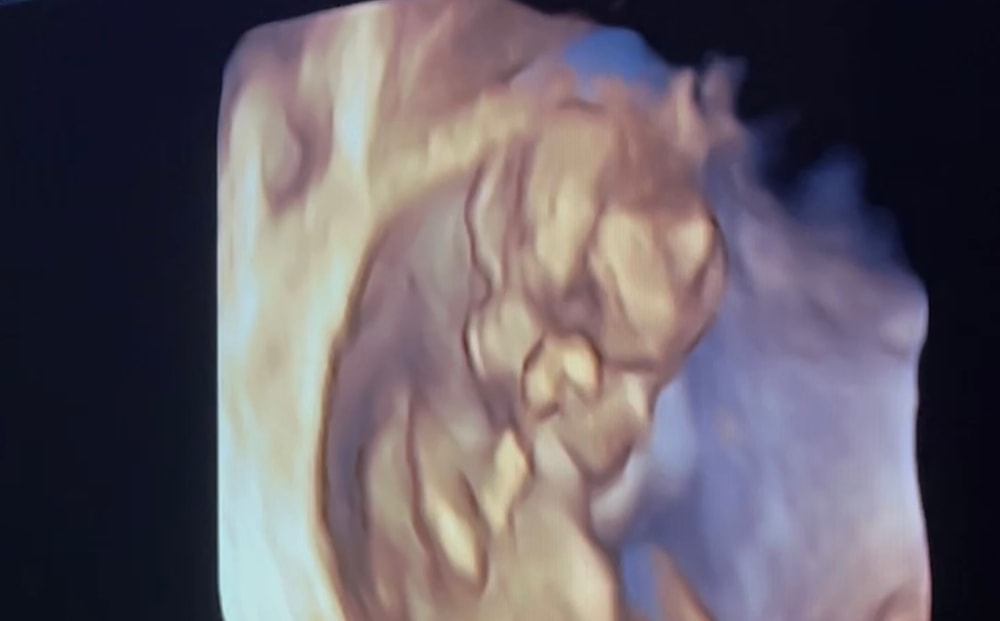

Мои 14 недель (где голова вверх направлена) и до этого 12 и 6 (где палец во рту) Изображение Изображение